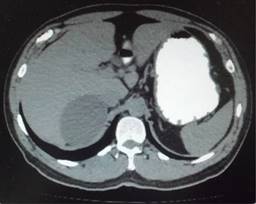

Biometría hemática, pruebas de función hepática, renales, TP y TPT de mayo de 2018 normales. No se realiza cortisol, aldosterona, catecolaminas urinarias ni metanefrinas. Tomografía de mayo reporta en glándula suprarrenal derecha imagen hipodensa con diámetros máximos de 101 mm, calcificaciones en su interior con efecto ocupativo y compresivo sobre las estructuras vecinas (Figuras 3 a 6). Completándose su valoración preoperatoria por medicina interna, se programa abordaje quirúrgico anterior abierto y bajo profilaxis antibiótica con ceftriaxona 2 g en dosis única, se realiza incisión subcostal derecha, destechamiento con electrocauterio de quiste suprarrenal derecho de 10 × 9 cm, con adherencias al hígado, contenido de aproximadamente 400 ml de líquido hialino y calcificaciones de alrededor de 20 × 40 mm en su interior. Se coloca drenaje abierto, penrose de ½” (19 mm) en espacio subfrénico ante la sospecha de hemorragia postoperatoria.